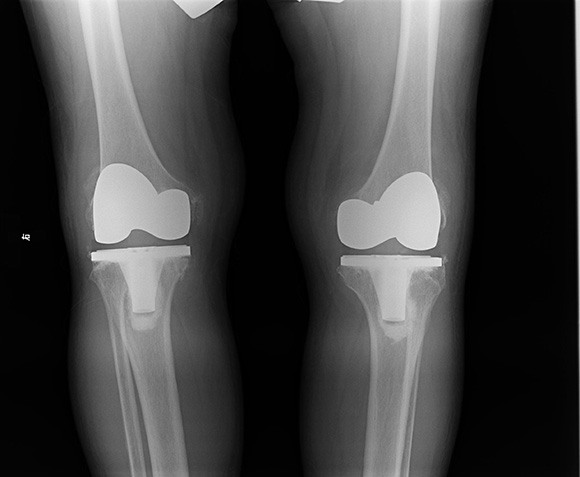

人工关节置换术是指采用金属、高分子聚乙烯、陶瓷等材料,根据人体关节的形态、构造及功能制成人工关节假体,通过外科技术植入人体内,代替患病关节功能,达到缓解关节疼痛,恢复关节功能的目的。目前,膝关节置换和髋关节置换是人工关节置换术中最常见的两类手术,更有80%以上的患者可以正常使用植入的假体长达20年以上,甚至伴随其终生。

图4.人工膝关节置换手术治疗重度膝关节骨性术后